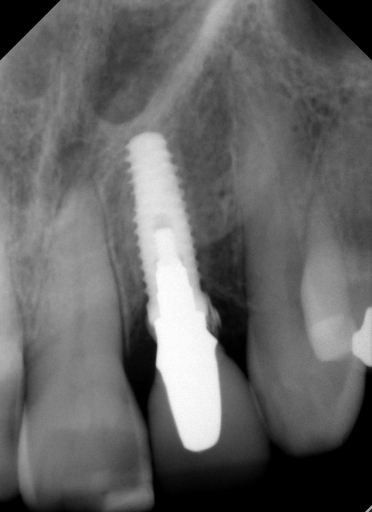

The surprise came when we took our final radiograph:

We couldn’t believe what we saw! How on earth did I leave such a large piece of cement? I mean, seriously, I was using RMGI cement that is easy to clean up, and we had done a custom abutment, so the margins were super accessible. We went after the debris and felt like we got some out, but honestly not as much as we expected, so we took another radiograph to see how we were doing. Here’s what we saw: